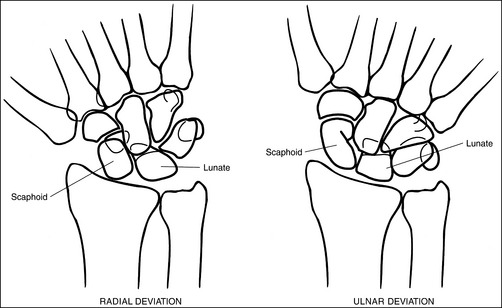

The long axes of the third metacarpal and the midforearm are aligned with the long axis of the collimated light field. The scaphoid and half of the lunate are positioned distal to the radius.

• If the long axes of the third metacarpal and the midforearm are aligned with the long axis of the collimated light field, the patient's wrist has been placed in a neutral position. If a neutral position is not maintained for a PA wrist projection, the shapes of the scaphoid and the position of the lunate are altered (Figure 4-33; see Images 36 and 37). Radial deviation of the wrist causes the distal scaphoid to shift anteriorly (toward the palmar surface) and to demonstrate increased foreshortening as it forms a signet ring configuration. The lunate will shift medially, toward the ulna. In ulnar deviation, the distal scaphoid tilts posteriorly and demonstrates decreased foreshortening, and the lunate shifts laterally, toward the radius. Radial and ulnar deviated PA wrist projections may be specifically requested to demonstrate wrist joint mobility.

Figure 4-33 PA wrist in radial deviation (left) and ulnar deviation (right). (From Martensen K II: Radiographic positioning and analysis of the wrist, In-Service Reviews in Radiologic Technology, 16[5], 1992.)

It is the hand position that varies the shape of the scaphoid. If the wrist is flexed as a result of hand extension or is radially flexed, the scaphoid is foreshortened. If the wrist is extended as a result of hand flexion or is ulnar-flexed, the scaphoid is demonstrated with decreased foreshortening. The shape and location of the lunate also vary with the position of the wrist and hand. It becomes triangular with hand extension and flexion and changes position in reference to the distal radius with radial and ulnar flexion. In radial deviation the lunate is positioned distally to the radioulnar articulation, whereas in ulnar flexion it is positioned distally to the radius.

Because the shapes of the scaphoid and lunate can be changed with more than one positioning movement, it is necessary to evaluate mispositioned images carefully to determine which movement is causing the misposition. It is also possible for two corrections to be needed simultaneously to obtain accurate positioning. The accuracy of hand flexion and extension are easily identified by evaluating the CM joints. Wrist ulnar or radial deviation is identified by evaluating the alignment of the third metacarpal with the radius.